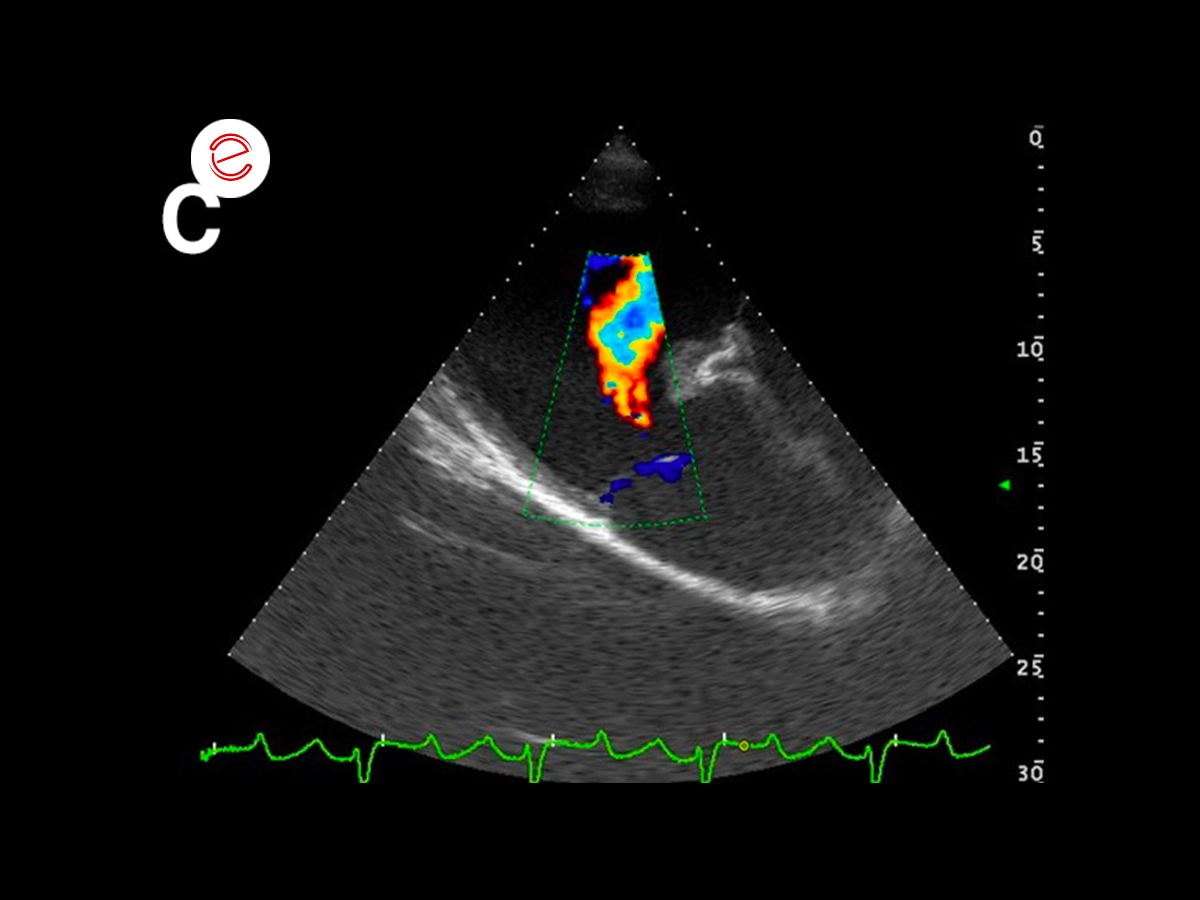

Right parasternal 4 chamber view (A) and left parasternal view of the left atrium and ventricle: significant dilation of the left atrium (v 166,4 mm; v.n 116 ± 7 mm) and the ventricle (systolic v 163.2 mm; v.n 112 ± 8 mm – diastolic v. 86.7) which present a globular aspect.

Right parasternal 4 chamber view (A) and left parasternal view of the left atrium and ventricle: significant dilation of the left atrium (v 166,4 mm; v.n 116 ± 7 mm) and the ventricle (systolic v 163.2 mm; v.n 112 ± 8 mm – diastolic v. 86.7) which present a globular aspect.

These images show: A) severe aortic regurgitation jet, B) severe mitral regurgitation jet; C) mild pulmonary regurgitation jet.